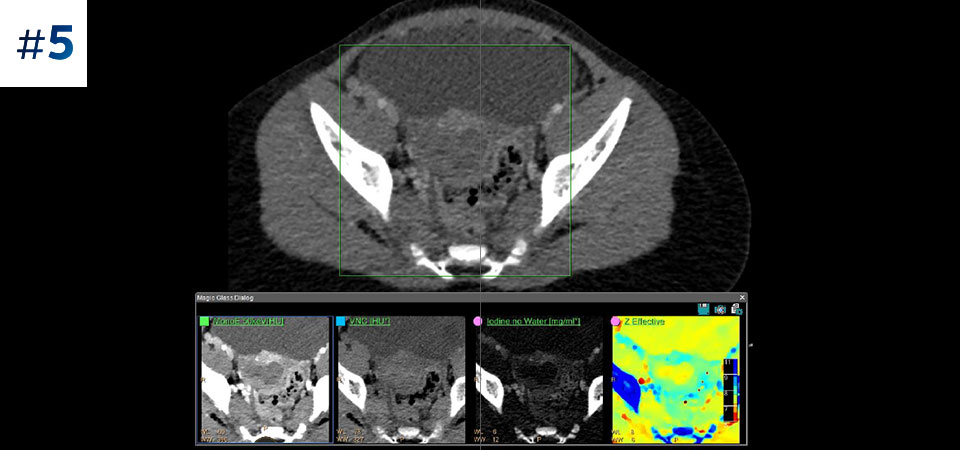

Reduced follow-up exams Improved tissue characterization and visualization may reduce the need for follow-up scanning for sub-optimal exams and incidental findings.

Go beyond conventional CT. See how layers of spectral-detector results can enhance your diagnostic confidence.